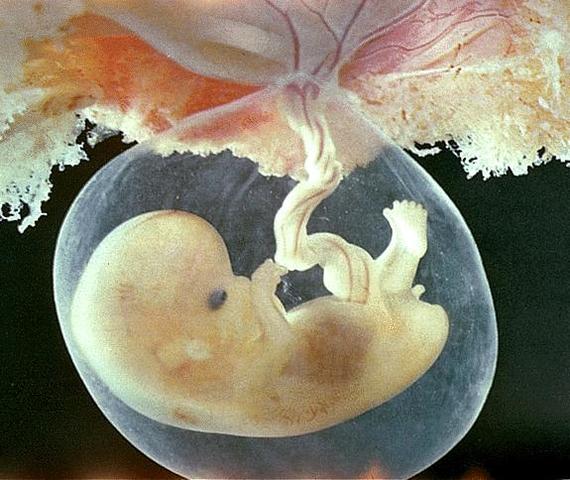

Se desarrolla el embrión,que tiene básicamente una cabeza,un tronco y una cola rizada; empieza a desarrollar los cimientos de lo que serán sus órganos, sus rasgos y su sistema nervioso.

Aparecen dos pequeñas cavidades oculares y la formación de sus orejas y los ojos entran en una fase primaria.

La placenta, que es el órgano que nutrirá al bebé en los próximos nueve meses, también se empieza a formar. Tu volumen de sangre aumenta en un 50%, para afrontar la demanda de oxigeno del feto